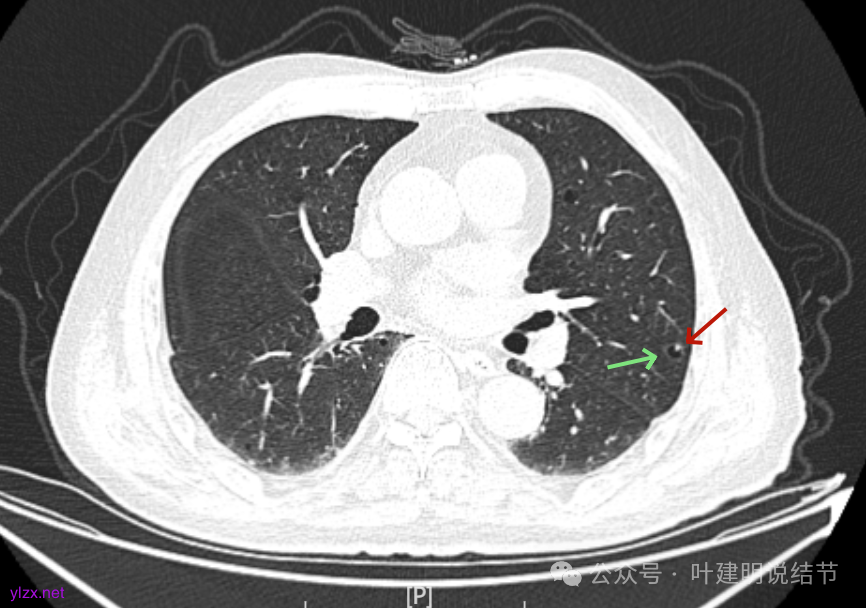

病灶囊壁稍不均,多密度较高,表面欠平。

病灶整体的囊壁稍不均,靠内侧有磨玻璃成分。

囊壁不厚但密度较高。

囊腔内壁稍显不光滑,有少许突起于囊腔内。

上图也见囊腔内壁有突起,此层囊壁大部分呈磨玻璃密度。

边缘区是淡磨,内壁少许突起。

矢状位见病灶囊壁有结节状高密度。

左肺上叶红色这处是囊腔型病灶,囊壁略不均,似有微小血管进入囊壁,对比2023年4月整个囊腔来讲有扩大,需要考虑囊腔型肺癌的可能性大。右侧蓝色的并不是典型囊腔型肺癌的表现,再加上两肺绿色这些慢支肺气肿与肺大泡的影像,右侧的就更加不确切,至少近期不能够考虑右侧也要开刀的事情。其实左侧的主病灶相对于其他表现更典型的囊腔型肺癌来说,由于囊壁密度偏高,也不是百分百必定是肺癌。我的想法还是先等脑梗情况稳定,并且间隔4~6个月复查病灶再有进展在考虑单孔胸腔镜下局部切除就可以。淋巴结可以考虑采样,但一般不至于阳性。破是不会切破的。消融不建议,囊腔灶更难通过穿刺获得病理依据,况且东西在边上,能局部楔切,当然首选手术。意见供参考!

左侧这个病灶总体上看仍是囊腔型肺癌可能性大些,但因为其两肺存在多发肺大泡的基础,而且囊壁除了结节状高密度的以外,其他的部分虽欠均匀,但差别并不太大。所以100%恶性还是难以认定的。假如没有脑梗情况,位置在边上,早点切了明确并去除病灶当然是可行的。但在反复脑梗发作的情况下,本身要神经内科情况稳定再手术较为安全,加上无法确切认定必恶性,再适当的随访也不至于影响预后。所以仍是利弊权衡与如何平衡的事情。对于这种囊腔灶,或囊肿为表现的肺癌,其实穿刺不容易阳性,针越过组织的距离并不长,其内又是空的或是液体性质的。从临床经验来看,囊腔型肺癌若囊壁是实性的,确实低分化类型的更常见些,相对风险较高些。但若是囊壁磨玻璃成分的,则也仍是贴壁为主型多见。而且从大小来讲,个人总觉得囊腔部分不能算大小,肿瘤的有形成分应该是减去空腔部分的,所以不能认定CT上测量的包括囊腔部分的来算肿瘤大小的T值。